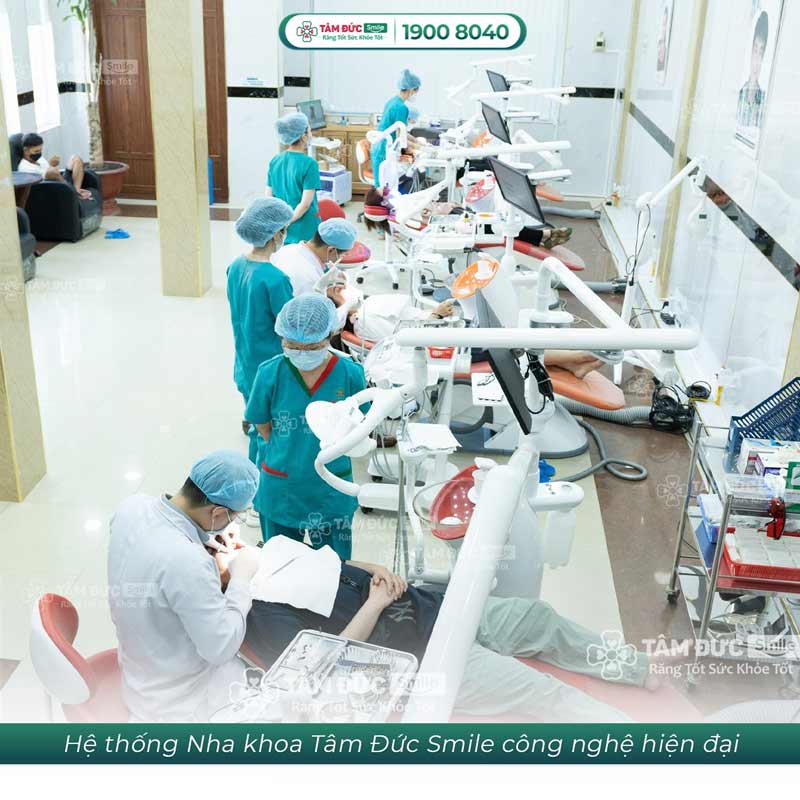

3. Nhổ răng khôn an toàn, hiệu quả tại nha khoa Tâm Đức Smile

Nha khoa Tâm Đức Smile là một trong những địa chỉ nha khoa uy tín, cung cấp dịch vụ nhổ răng khôn an toàn. Tâm Đức Smile áp dụng công nghệ nhổ răng khôn hiện đại, giúp quá trình tiểu phẫu diễn ra nhanh chóng, nhẹ nhàng, hạn chế xâm lấn, mau lành thương.

Quy trình nhổ răng khôn tại nha khoa Tâm Đức Smile được thực hiện theo tiêu chuẩn của Bộ Y tế, đảm bảo an toàn tuyệt đối. Các bác sĩ tại nha khoa đều là những chuyên gia giàu kinh nghiệm, được đào tạo bài bản với thao tác nhổ răng nhẹ nhàng.